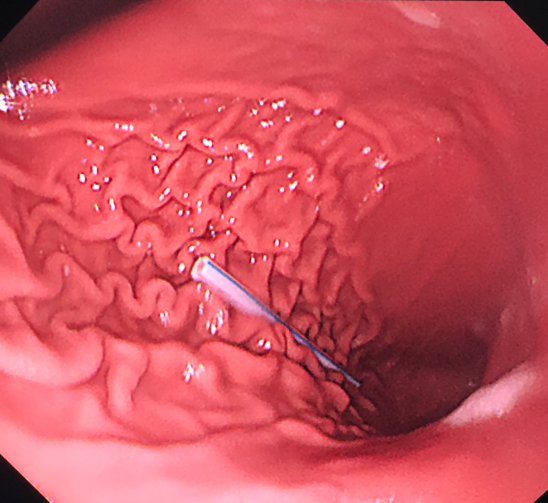

- 内镜下圈套包裹取出的螺纹钉 -

内镜下医生发现孩子的胃肠道黏膜已经有损伤、糜烂。并且随着肠道蠕动,螺丝钉现已移动到十二指肠远端。

经验丰富的李中跃主任,当即决定用圈套圈住螺纹钉近端后取出。